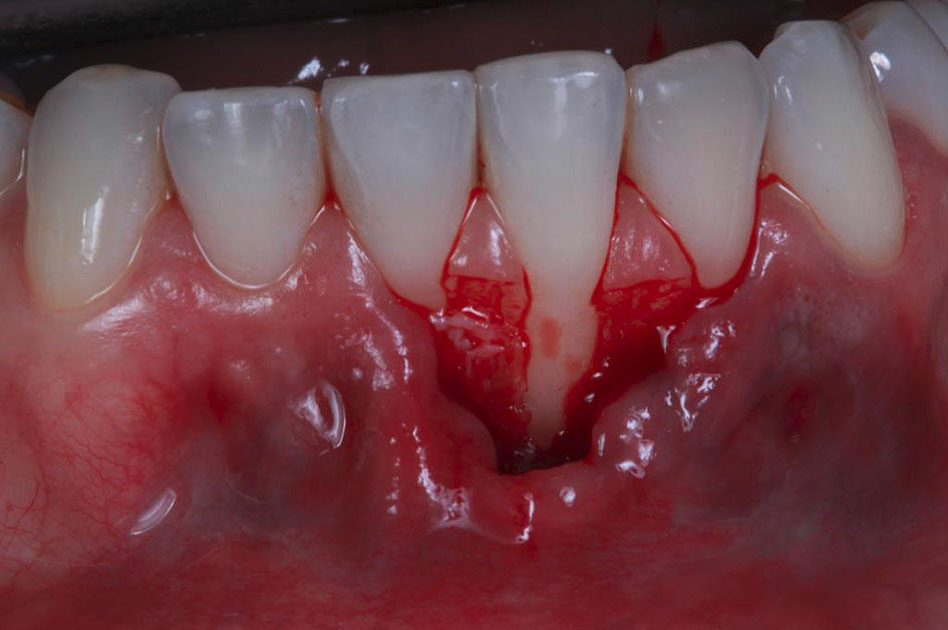

Figure 2.

Horizontal incision at the papilla base with blade #15C.

After measuring the receptor area, a mesiodistal (6 mm) SCTG was harvested from the palate at a 1-mm thickness using a double-blade scalped blade. The epithelial layer was removed during the preparation of the SCTG.13 Before the SCTG insertion (Figure 3), 24% EDTA (Straumann PrefGel, 24% EDTA, Straumann Group) was applied for root surface biomodification for 2 minutes, followed by applying enamel matrix proteins (Emdogain, Straumann Group, Switzerland).

Figure 3.

Sutures were performed to keep the SCTG and the flap in position.